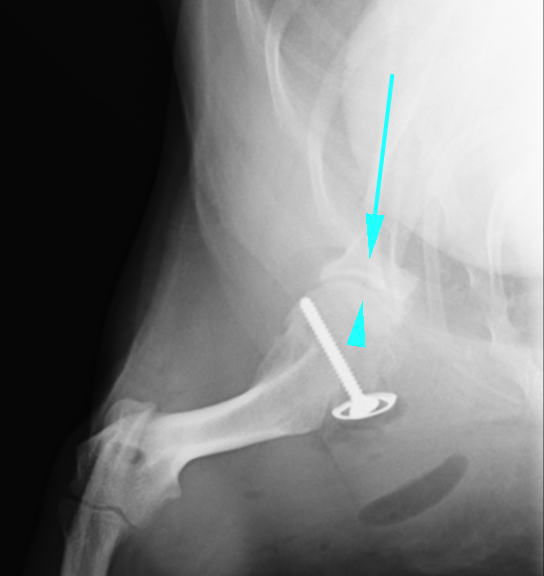

左の肩関節を内側から見た解剖学的な位置です。緑の矢印が上腕二頭筋腱です。それを左側(尾側)に移動させ、ワッシャーとスクリューで固定させます。そうすることで上腕二頭筋腱が肩甲骨と上腕骨を強く引っ張り脱臼しないようになります。場合によっては肩甲骨にスクリューアンカーを打ち、糸による靭帯強化を行う場合もあります。

術後のX線画像です。ワッシャーとスクリューが入っているのが確認できます。また、ずれていた矢印の骨がぴったりと合い、関節がはまっているのがわかります。